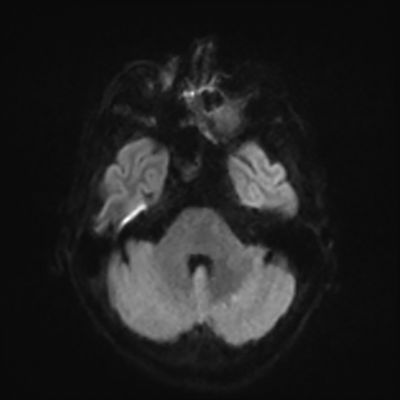

MRI brain (DWI)

MRI brain (DWI) 4/24 4/24

You can clearly see diffuse cortical and basal ganglia diffusion restriction, and that of his deep cerebellar nuclei as well. The right occipital lobe abnormalities are a little more prominent, but then you remember that he is known to have had a right occipital stroke weeks ago.

In reviewing his data, you know that he doesn't have any of the strong predictors of a poor neurologic prognosis. However, based on these findings on MRI, along with the absent reactivity on cEEG, you are able to tell the primary team and the patient's family that he is likely to have a poor prognosis, based on these multiple moderate predictors. Recovery is not completely impossible-- there is more uncertainty with this prognostication than if we were able to get SSEPs-- but you're very worried about his outlook and that any potential recovery would require a very protracted rehabilitation period. Given his high cervical cord injury level, tracheostomy would be required anyway. So, it comes down to whether his family thinks he'd want to pursue these aggressive measures.